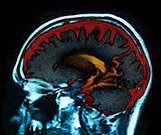

T2DM Linked to Declines in Cerebral Vasoreactivity, Cognition

Neuropsychological performance declined noticeably in just two years